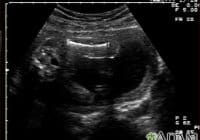

“Puan, femur length baby macam tak ikut jadual perkembangan yang sepatutnya. Saya akan rujukkan puan ke Hospital Selayang.” Lembut saja tutur kata doktor di Klinik Kesihatan (KK) tatkala selesai proses ultrasound pada minggu ke 29 bulan lalu. Pernyataan lembut tapi bedebush dalam fikiran saya, risau ada, sedih pun ada. Tapi pada masa yang sama saya … Continue reading Bila Perkembangan Bayi Dalam Kandungan Delay